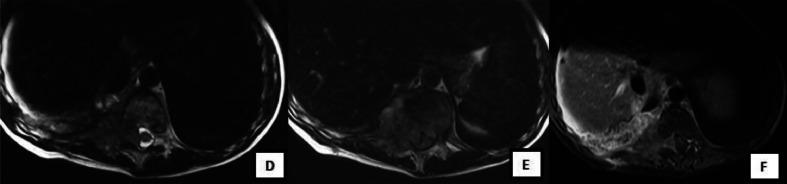

Nephroblastoma or Wilms' tumor is the most common malignant tumor of the kidney in the pediatric population. Metastasis is caused by hematogenous spread. The most common localizations in decreasing order of frequency are lymph nodes, lungs, and liver. The bone is very rarely affected. According to the literature, bone metastases have been described in the iliac bone, skull, and mandible. The vertebral localization was described in 3 cases only, the first 1 in 2009, and the 2 others in 2015 . The goal of our work is to report a very rare case of metastatic vertebral localization of a Wilms' tumor in relapse after treatment; and thus to underline the potential for vertebral and intracanal involvement in nephroblastoma.

肾母细胞瘤或威尔姆斯瘤是儿童人群中最常见的肾脏恶性肿瘤。转移是由血行播散引起的。按频率递减顺序排列,最常见的转移部位是淋巴结、肺和肝。骨骼很少受累。根据文献记载,已有髂骨、颅骨和下颌骨发生骨转移的报道。仅3例报道了椎体转移,第一例于2009年报道,另外两例于2015年报道。我们这项工作的目的是报告1例治疗后复发的威尔姆斯瘤发生椎体转移的罕见病例;从而强调肾母细胞瘤累及椎体和椎管的可能性。